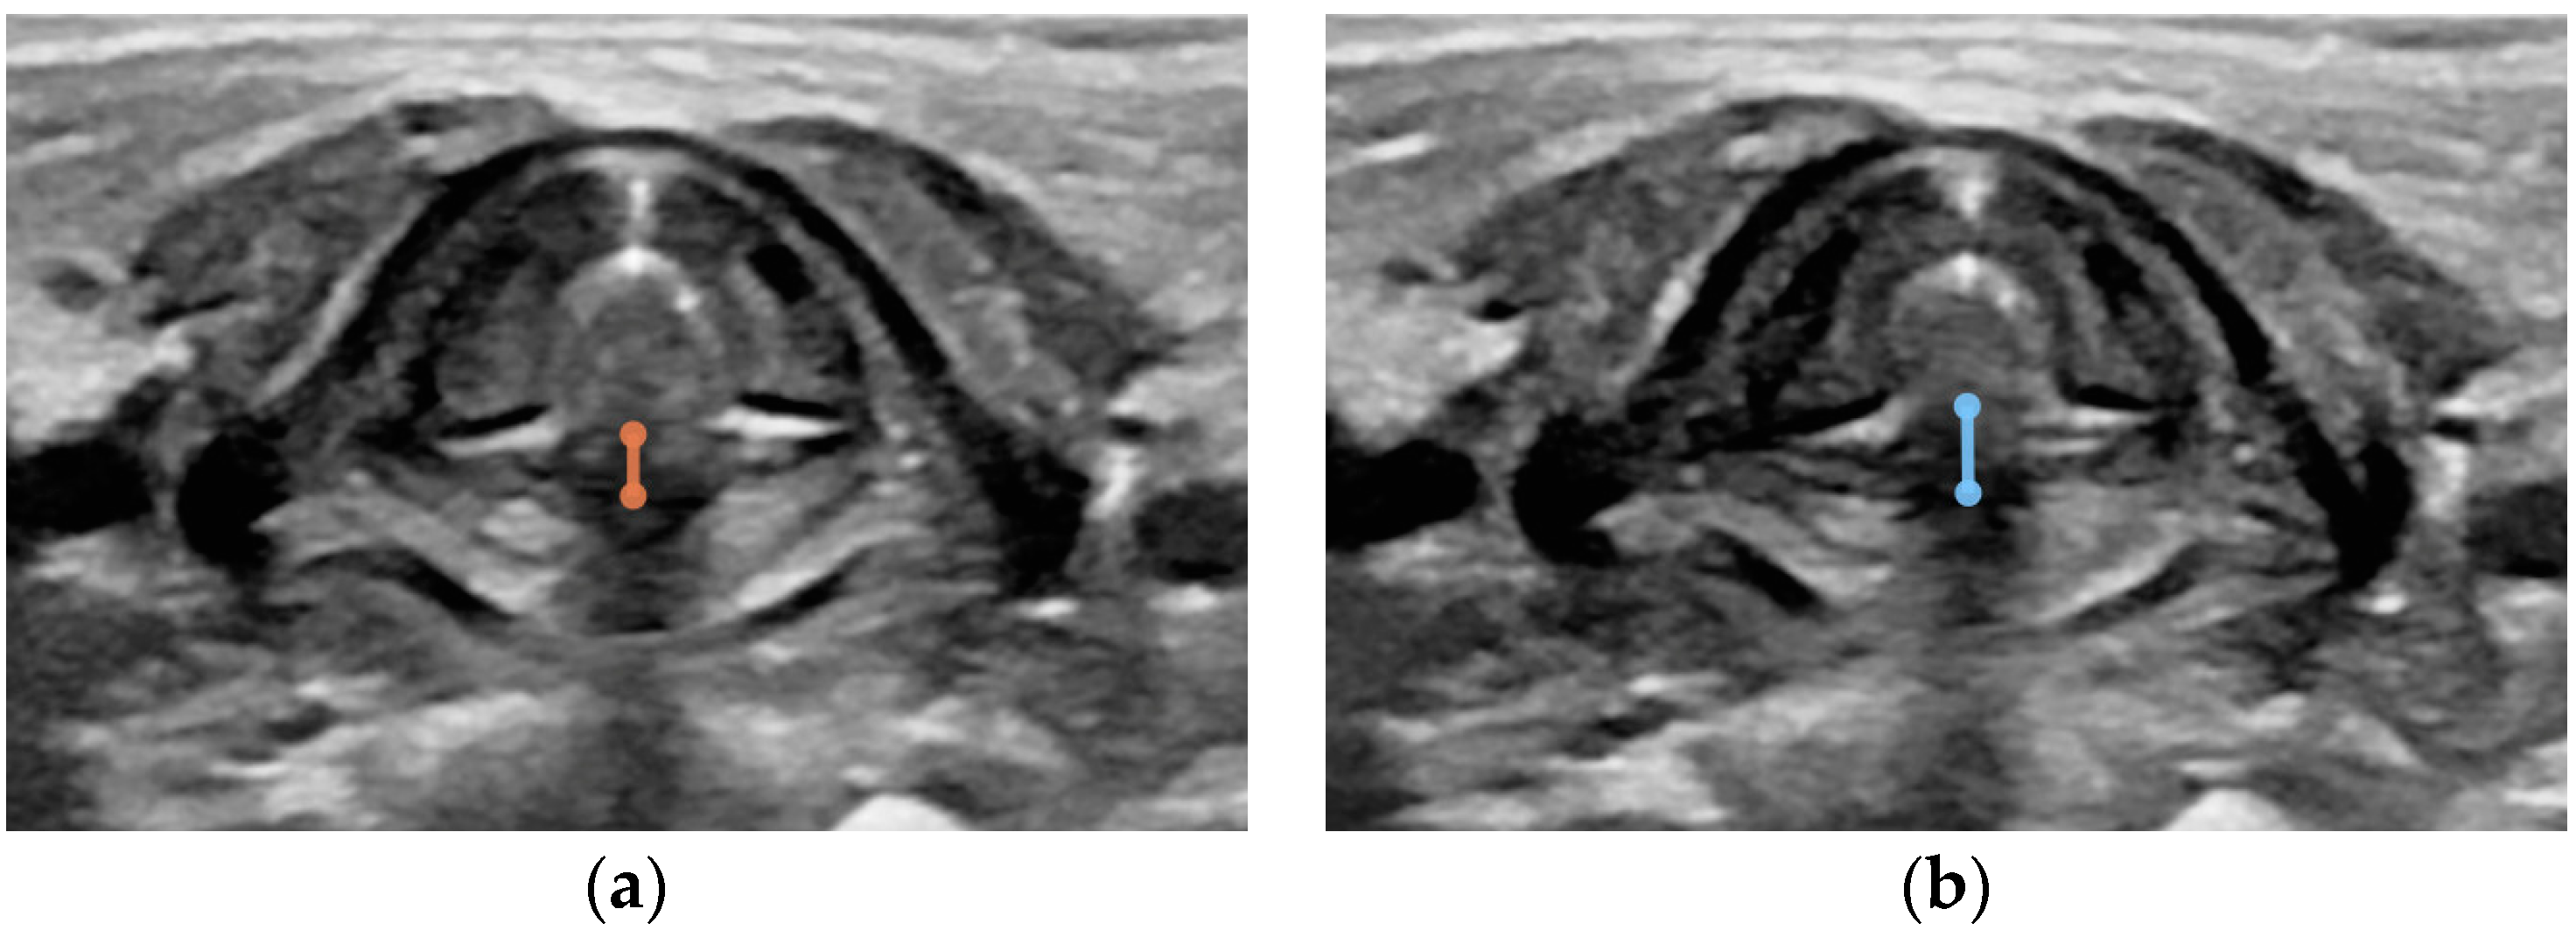

- Thickness of the thyroid cartilage in the midline and on both sides transversely at the level of the glottis (in the transverse plane measurement from external margins of thyroid cartilage and vertical measurement of thyroid cartilage above the anterior commissure at the level of well-visualized arytenoid cartilages in the transverse plane) (Figure A3);